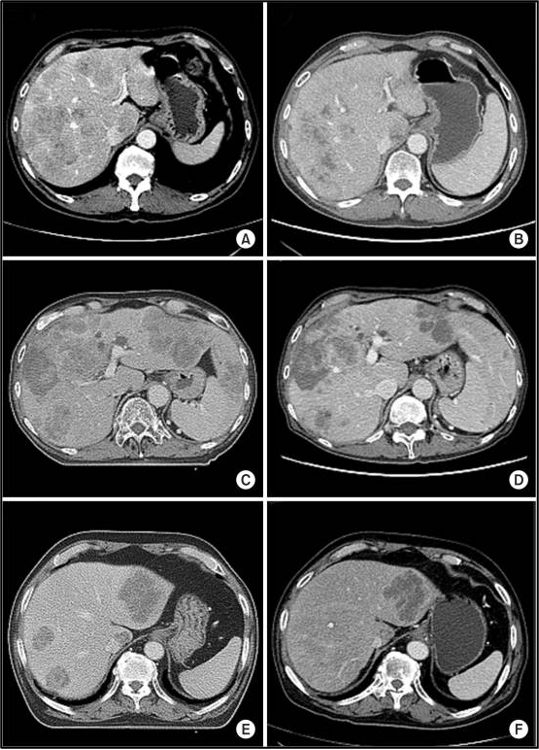

מתוך 10 המטופלים שקיבלו טיפול קרינתי לכל הכבד (WLI) עם היפרתרמיה, מחלה פרוגרסיבית (PD) של גרורות בכבד נצפתה בשני מטופלים (20%), ושלושה הציגו תגובה חלקית (PR) (איור 2). לאחר חודשיים, השלושה האחרים הציגו מחלה פרוגרסיבית (PD) בכבד, ושלושה נותרו ללא מחלה פרוגרסיבית (PD-free) 3 חודשים לאחר הטיפול.

להלן איור 2 : שינויים בתמונות ההדמיה של טומוגרפיה ממוחשבת (CT) לאחר טיפול קרינתי לכל הכבד (WLI) בשילוב עם היפרתרמיה: 3 מתוך 10 מטופלים הדגימו תגובה חלקית (partial response) חודש אחד אחרי הטיפול. תמונות הדמיית CT שנלקחו לפני (A,C,E) וחודש אחרי WLI (F,D,B)